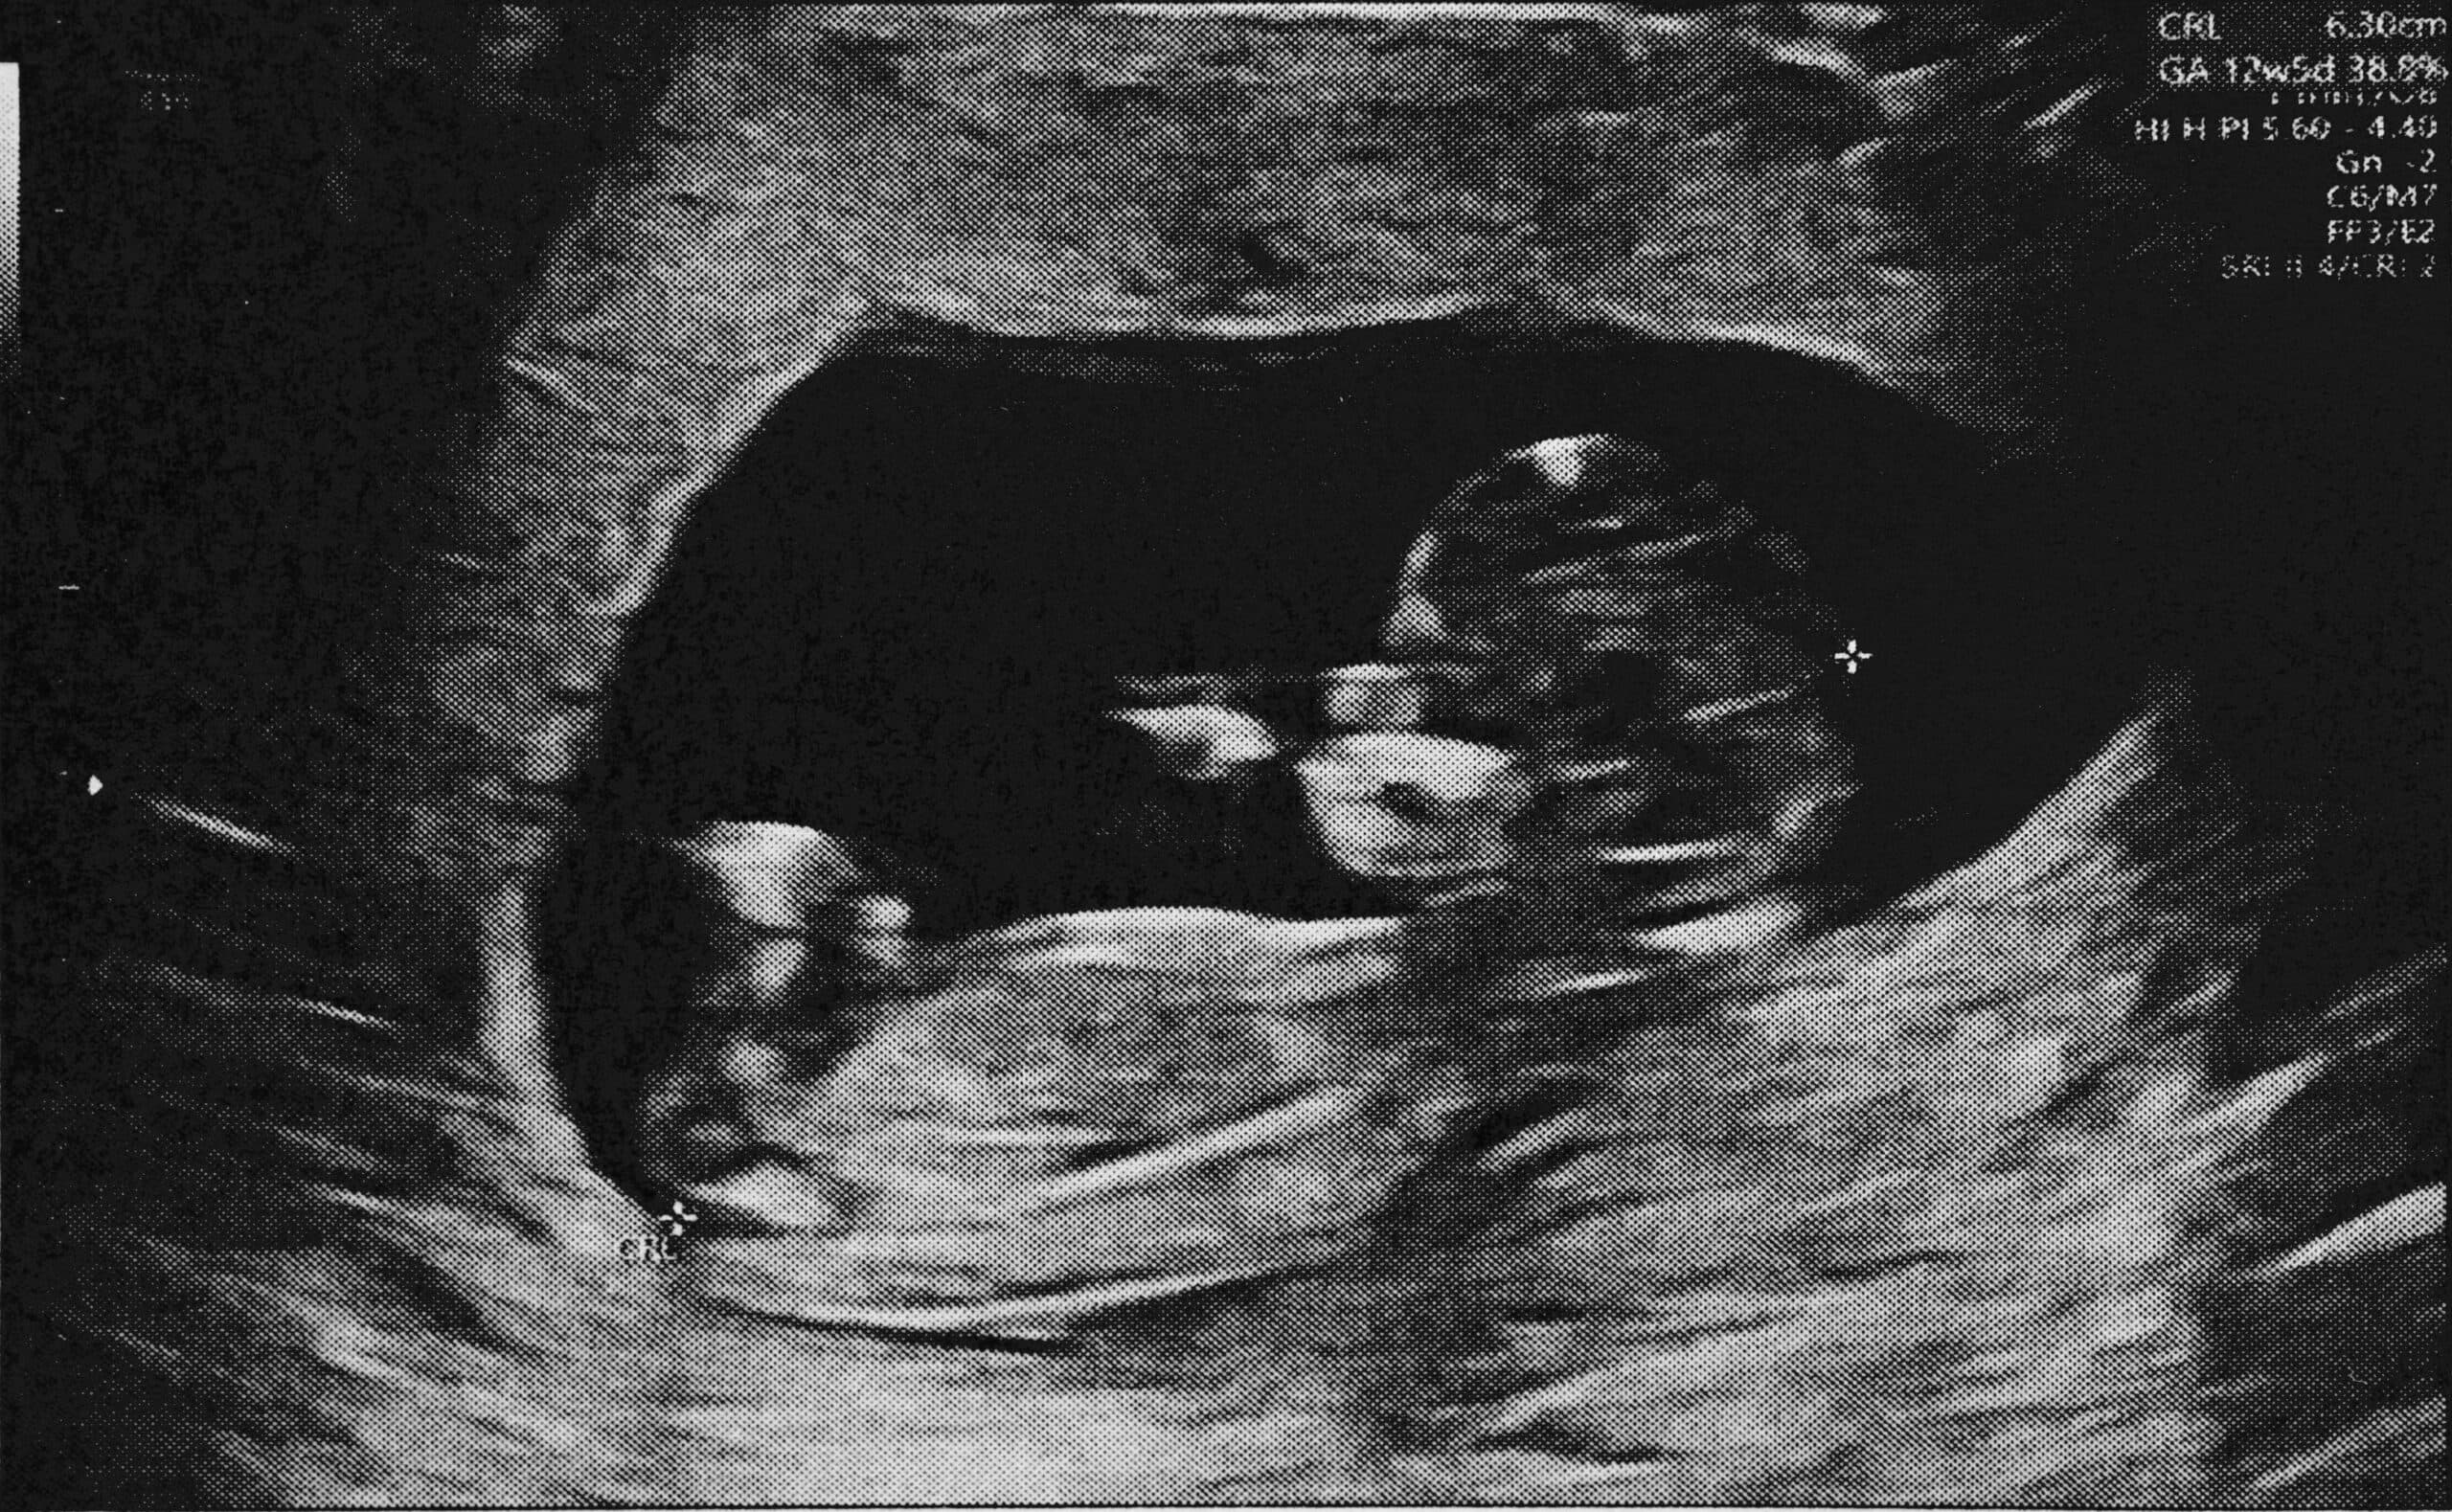

Ersttrimesterscreening

Das Ersttrimesterscreening, durchgeführt zwischen der 11. und 14. Schwangerschaftswoche, ist ein wichtiger Bestandteil der pränatalen Diagnostik. Es bietet werdenden Eltern frühzeitig Einblicke in die Gesundheit und Entwicklung ihres ungeborenen Kindes. Einer der Schlüsselparameter in diesem Screening ist PAPP-A (pregnancy-associated plasma protein A), welcher aktuell als einer der aussagekräftigsten biochemischen Marker aus dem ersten Trimenon für die statistische Präzisierung des Risikos von Chromosomenanomalien angesehen wird. Zusammen mit der sonografisch gemessenen Nackentransparenz des Fötus und optional dem freien β-hCG (humanes Choriongonadotropin) im mütterlichen Blut ermöglicht es, ein statistisches Risiko für Chromosomenanomalien im ersten Trimenon zu berechnen.